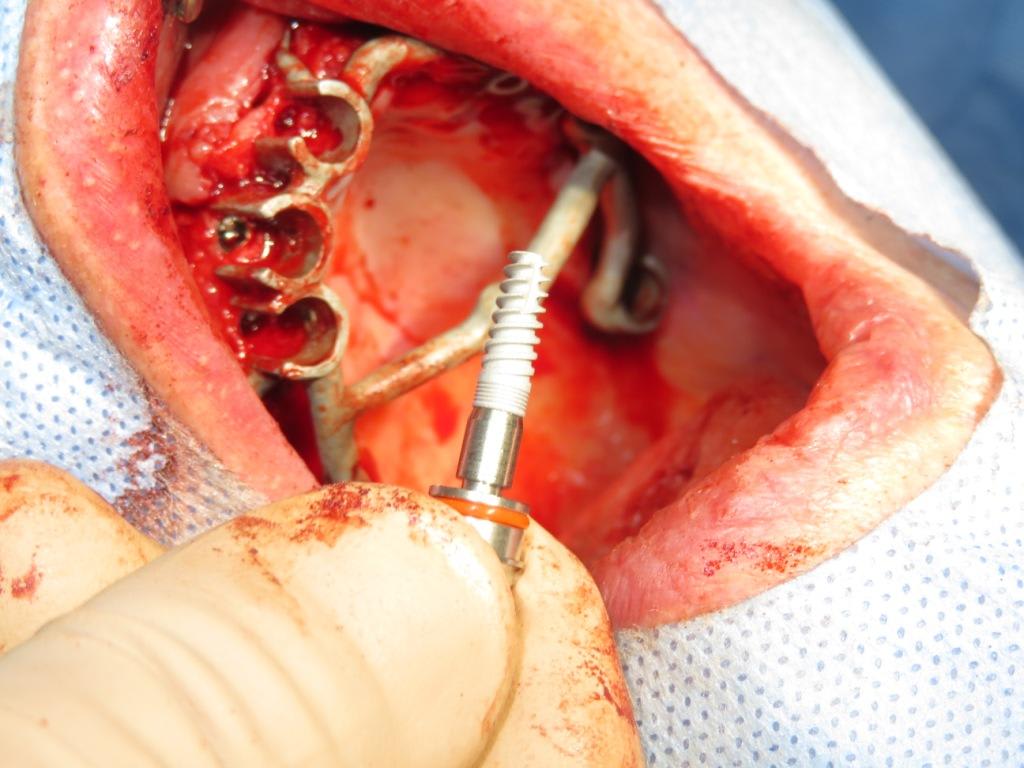

perso, je préfère ne pas perdre de temps (cf les repère chronologiques début-fin d'intervention) because time is money (et pour ce cas fait avec Alain, pas plus tard qu'hier, je ne suis pas à beaucoup plus de 10k€....)

Img 0001 axxxt4 - Eugenol

Img 0006 xdcmx3 - Eugenol

Img 0014 n2v53o - Eugenol

Img 0015 brdpvh - Eugenol

Img 0025 kzv3w5 - Eugenol

Img 0027 fwlgnt - Eugenol

Img 0037 n9s4o6 - Eugenol

Img 0038 yrxw5n - Eugenol

Img 0055 c9kovc - Eugenol

Img 0056 wzvlkq - Eugenol

Img 0063 vsmdns - Eugenol

Img 0072 irdf5w - Eugenol